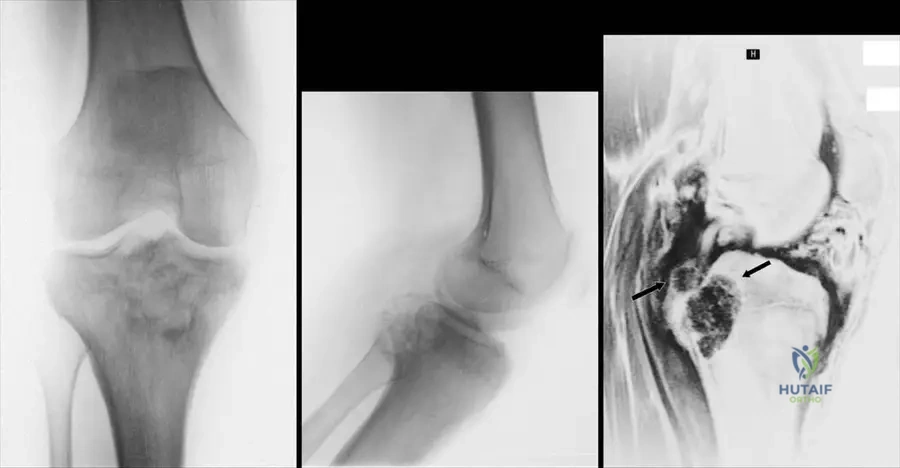

A 16-year-old male presents with chronic knee pain that has been present for several years. Physical examination reveals tenderness around the knee. Radiographs show a lytic lesion in the proximal tibial epiphysis. An MRI confirms an epiphyseal lesion.

View Answer & Explanation

Correct Answer: C

Rationale: Chondroblastoma is a benign cartilage-producing tumor typically found in the epiphysis or apophysis of adolescents or young adults, often presenting with chronic pain. The age (16-year-old) and epiphyseal location are classic for chondroblastoma. Main Distractor: Giant Cell Tumor (GCT) typically occurs in a slightly older age group (20-40s) and usually involves the epiphysis after physeal closure, although it can cross the physis.

Question 54

A 16-year-old male presents with chronic knee pain. Radiographs reveal a lytic lesion in the proximal tibial epiphysis. An MRI confirms an epiphyseal lesion. The patient's pain has been present for an extended period.

Correct Answer: B

Rationale: The clinical context states that matrix calcifications are present in approximately one-quarter of chondroblastomas, making this a characteristic radiographic feature, though not universally present. Main Distractor: A sclerotic rim can be seen in some benign lesions, but matrix calcifications are specifically highlighted for chondroblastoma.

Question 58

A 16-year-old male presents with knee pain. Imaging reveals a lytic lesion located in the epiphysis of the proximal tibia. The patient has open growth plates.

Rationale: The text states that chondroblastomas "occur in primary or secondary ossification centers" and are "usually localized to the epiphysis or apophysis." Main Distractor: The metaphysis is a common location for many other bone tumors (e.g., osteosarcoma, osteochondroma), but chondroblastoma's predilection for the epiphysis/apophysis is a key diagnostic feature.

Question 60

A 16-year-old male undergoes biopsy of an epiphyseal lesion. Gross examination of the specimen shows areas of chondroid-appearing tissue as well as more cystic regions.

Rationale: The provided image context (Fig. 8.44) and text explicitly state that "Chondroblastomas can have components of secondary aneurysmal bone cyst," which explains the presence of cystic regions. Main Distractor: While simple bone cysts are cystic, the specific association mentioned in the text is with aneurysmal bone cysts.